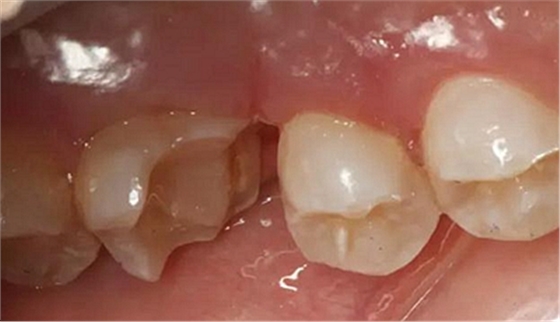

最后附幾例一次性根管治療+冠延長手術(shù)+高嵌體修復(fù)的病例,均為兩次完成。第一次就診:根管治療一次完成,后冠延長手術(shù),然后高嵌體預(yù)備,取模,第二次就診,拆線,試戴嵌體。具體在此不做詳細(xì)說明,圖中有詳解。

另外一個病例

病例3

該病例后期樹脂嵌體完成,為學(xué)生完成。沒有完成后的樹脂嵌體照片。病例已經(jīng)完成。